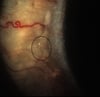

На данной фотографии показаны отдельные пенистые участки (бляшки Бито, отмеченные кругом) на конъюнктиве.